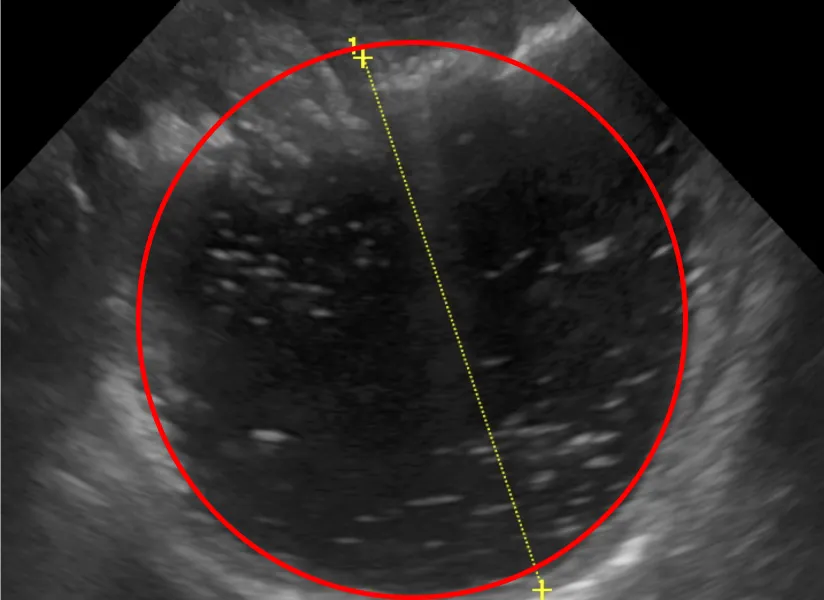

具体的には、糞便検査で感染症(寄生虫、細菌、ウィルスなど)の有無を、血液検査でスクリーニングをかけ内分泌疾患(ホルモン病)やその他の疾患を除外そして画像検査(レントゲン検査・エコー検査)で異物の誤飲、胃腸の動きや構造の変化などを確認します。

試験的治療で改善しない場合や、一般検査で異常があり追加検査が必要な場合などに精密検査を行います。例えば、エコー検査で腹腔内腫瘤があれば細胞診を、エコー検査では評価できない場合はCT検査を行います。